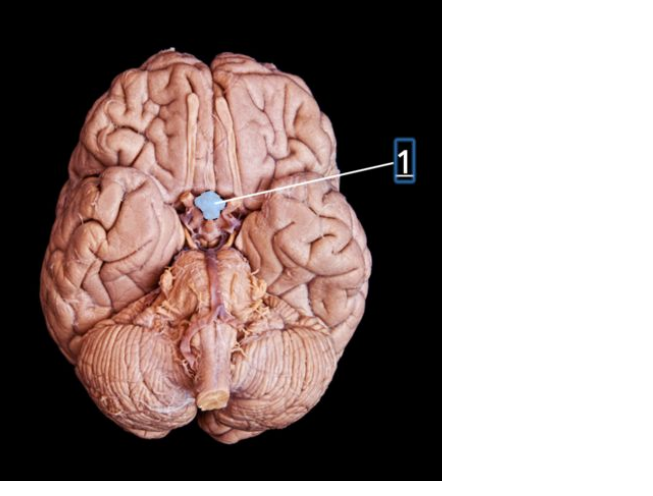

chiasma opticum

corpus mamillare dex.

a. basilaris

crus cerebri Dex.

corpus pineale

tractus olfactorius dex.

bulbus olfactorius